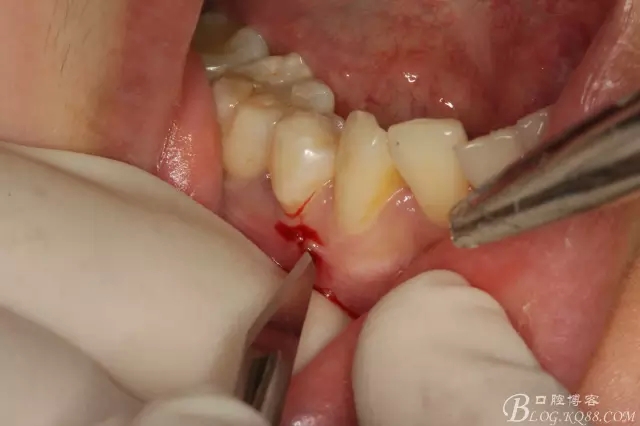

圖5.局部麻醉下、在44近中做垂直小切口,切口不要超過膜齦聯(lián)合。

圖6.齦溝內(nèi)水平切口